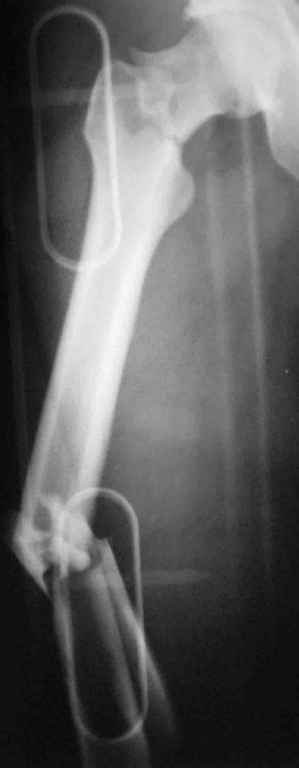

Уважаемый Сергей, избрав вариант DHS плюс ретроградный гвоздь Вы явно обезопасите себя от проблем, связанных с введением штифта через trochanteric fossa. Очень это может быть проблематично, Вы правы. Поэтому DHS плюс ретроградный гвоздь - спокойно выполнимый вариант, особенно в "чужом" отделении. Схожий свой случай из далёкого теперь уже 1999г. прилагаю, только вместо канюлированных винтов у Вас будет DHS (VHS). А если антеградный гвоздь - то только из тех, что предназначены к введению через верхушку вертела. И это тоже выполнимо, но сложнее. Мне так кажется.

Уважаемый Сергей Витальевич! Мы в похожем случае выбрали вариант DHS + DFN. Правда из 4 кортикальных винтов накладки DHS - 2 пришлось вводить монокортикально - уперлись в штифт.. На конечный результат это не повлияло. Ссылка здесь.